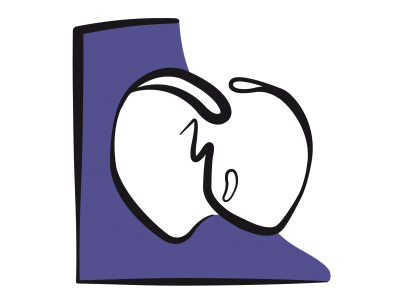

Mais si la cavité du VG se rétrécit au point que la paroi postéro-basale se déplace vers l’avant, le point de coaptation de la mitrale avance en direction de la chambre de chasse du VG (CCVG); l’occlusion n’a plus lieu sur le bord distal des feuillets mais entre l'extrémité du feuillet postérieur et le corps du feuillet antérieur. La partie distale de ce dernier flotte alors dans la cavité du VG, et l'élévation de la pression intraventriculaire la repousse antérieurement en direction de la CCVG. Par effet Venturi, elle est ensuite aspirée dans la CCVG, qu'elle occlut plus ou moins complètement. C’est le SAM (systolic anterior motion), qui survient en méso-systole (Figure 27.5) [4,17].

Figure 27.5 : Obstruction dynamique de la CCVG. A : situation normale. Le point de coaptation des feuillets mitraux est situé au tiers postérieur du diamètre antéro-postérieur (flèches bleues); en systole, la course radiaire de la paroi postéro-basale (*) est plus faible que celle de la paroi antéro-latérale; elle est activée électriquement en dernier. B: si le VG devient très petit par hypovolémie, la paroi postérieure avance en direction de la CCVG (flèche violette), parce que la zone antérieure est la jonction mitro-aortique qui est un point fixe (trigone fibreux); le point de coaptation est alors projeté vers la CCVG. En protosystole, la coaptation a lieu entre l'extrémité du feuillet postérieur et le corps du feuillet antérieur, dont la partie distale se retrouve flottant dans le VG et non en application contre le feuillet postérieur. C : en mésosystole, la pression intraventriculaire pousse le feuillet antérieur en direction de la CCVG (flèche violette) où l'éjection a commencé; celui-ci est alors aspiré par effet Venturi (flèche bleu pâle) et vient bloquer la CCVG (SAM: systolic anterior motion). Le débit aortique baisse soudainement, et la réouverture de la valve mitrale provoque une insuffisance méso-télésystolique (IM). MPP: muscle papillaire postérieur.

L’imagerie bidimensionnelle est le seul moyen de mettre en évidence un phénomène qui peut accompagner l’hypovolémie : l’obstruction dynamique de la chambre de chasse du VG ou effet CMO, par analogie avec la cardiomyopathie obstructive. Normalement, le point de coaptation de la valve mitrale est maintenu éloigné de la chambre de chasse par trois mécanismes: 1) il est situé au tiers postérieur du diamètre de la valve; 2) la paroi postérieure a moins de course radiaire que les parois antérieure et latérale; 3) la partie postéro-basale est activée électriquement en dernier (Vidéo). Lorsqu’elle s’élève en systole, la pression intraventriculaire maintient l’occlusion de la mitrale en appuyant les deux feuillets l’un contre l’autre par leurs bords distaux.

Mais si la cavité du VG se rétrécit au point que la paroi postéro-basale se déplace vers l’avant, le point de coaptation de la mitrale avance en direction de la chambre de chasse du VG (CCVG); l’occlusion n’a plus lieu sur le bord distal des feuillets mais entre l'extrémité du feuillet postérieur et le corps du feuillet antérieur. La partie distale de ce dernier flotte alors dans la cavité du VG, et l'élévation de la pression intraventriculaire la repousse antérieurement en direction de la CCVG. Par effet Venturi, elle est ensuite aspirée dans la CCVG, qu'elle occlut plus ou moins complètement. C’est le SAM (systolic anterior motion), qui survient en méso-systole (Figure 27.5) [4,17].

Figure 27.5 : Obstruction dynamique de la CCVG. A : situation normale. Le point de coaptation des feuillets mitraux est situé au tiers postérieur du diamètre antéro-postérieur (flèches bleues); en systole, la course radiaire de la paroi postéro-basale (*) est plus faible que celle de la paroi antéro-latérale; elle est activée électriquement en dernier. B: si le VG devient très petit par hypovolémie, la paroi postérieure avance en direction de la CCVG (flèche violette), parce que la zone antérieure est la jonction mitro-aortique qui est un point fixe (trigone fibreux); le point de coaptation est alors projeté vers la CCVG. En protosystole, la coaptation a lieu entre l'extrémité du feuillet postérieur et le corps du feuillet antérieur, dont la partie distale se retrouve flottant dans le VG et non en application contre le feuillet postérieur. C : en mésosystole, la pression intraventriculaire pousse le feuillet antérieur en direction de la CCVG (flèche violette) où l'éjection a commencé; celui-ci est alors aspiré par effet Venturi (flèche bleu pâle) et vient bloquer la CCVG (SAM: systolic anterior motion). Le débit aortique baisse soudainement, et la réouverture de la valve mitrale provoque une insuffisance méso-télésystolique (IM). MPP: muscle papillaire postérieur.